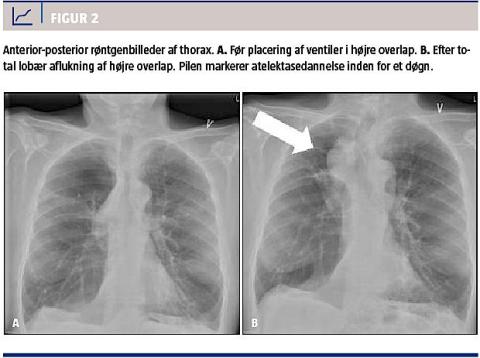

Princippet ved bronkoskopisk indsættelse af envejsventiler i luftvejene er aflukning af dele af lungen. Når ventilerne er placeret, kan der ikke længere komme luft ind i de behandlede segmenter, mens den eksisterende luft og eventuelt sekret kan passere ud af ventilen. På den måde dannes der en atelektase, og der opnås lungevolumenreduktion (Figur 2).

Der findes flere forskellige metoder til bronkoskopisk volumenreduktion. Den hyppigst anvendte er indsættelse af endobronkiale ventiler, hvilket er den mest gennemprøvede, men andre muligheder er airway stents eller coils, brug af polymerskum eller vanddamp. Indikationen for de forskellige modaliteter fremgår af Tabel 2 og Figur 1.